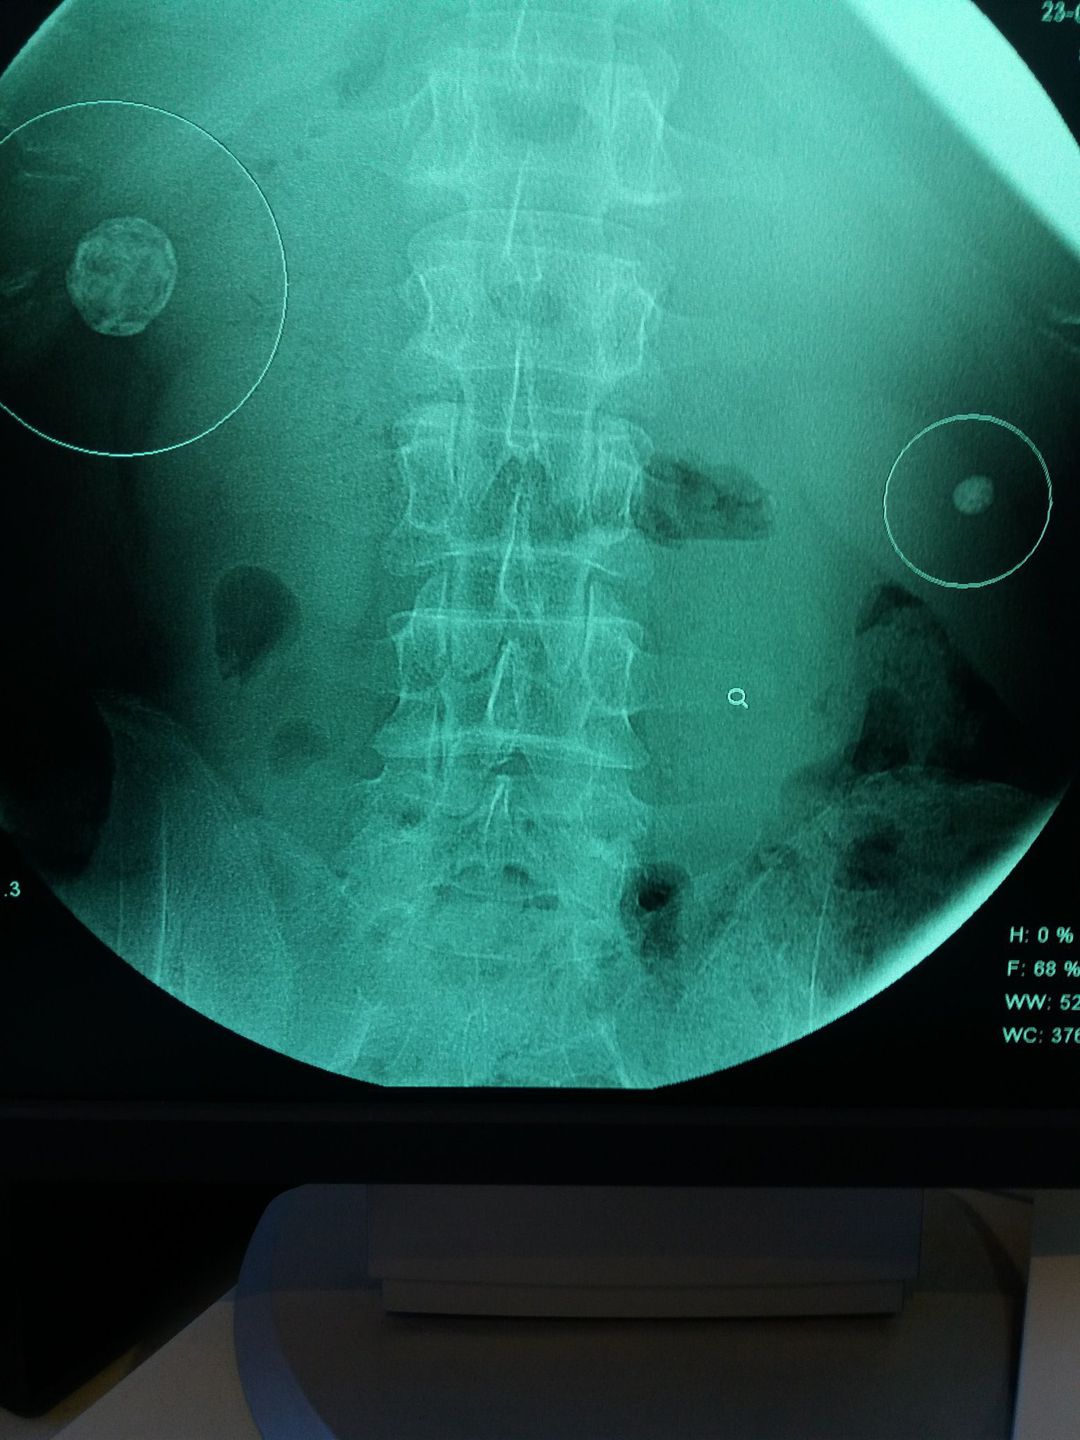

Gall stones and right kidney stoune

Xray

Gallbladder

Stouns